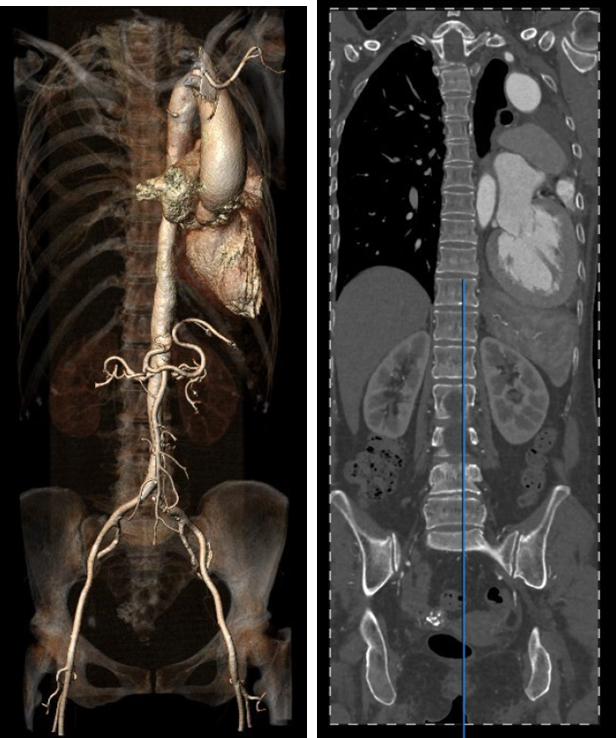

患者17年前因肺结核行左肺叶切除,术前CT结果显示,心脏转位完全偏至左侧胸腔,主动脉弓被挤压成角非常锐利。患者为二叶式主动脉瓣 Type 1型,R-L融合大块钙化脊,且钙化赘生物垂坠至瓣环平面,导致“lazy leaflet”瓣叶结构,主动脉根部极重度钙化,风险度极高,球囊扩张时合并极高的瓣环破裂风险,也可能无法推动钙化使瓣膜形态变形导致严重瓣周漏等并发症。瓣环面积为588.8mm2,平均内径为27.4mm。考虑到患者已行开胸手术,身体虚弱,外科手术风险较高,且介入治疗可更快恢复,减少住院时间,经心脏团队讨论,并与家属协商后,计划行经导管主动脉瓣置换术。

图1. 左肺叶切除后心脏转位,主动脉弓挤压成角锐利